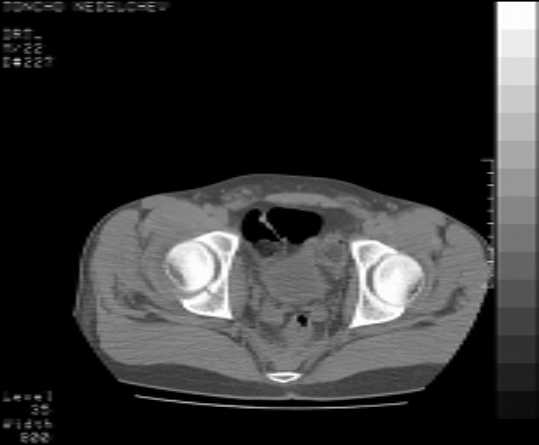

Here are some more axial images. What is your opinion as for the timing of the operative treatment?

The details of the fracture are not so clear from the images sent...would you be able to send along an AP and Judet images as well as some additional axial images above and below the joint?